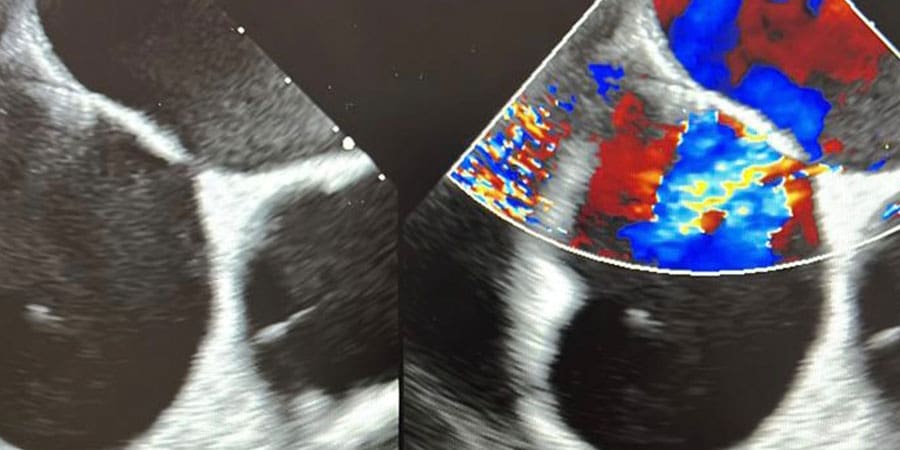

تمكن فريق طبي في مستشفى جامعة السلطان قابوس من إجراء عملية قسطرة ناجحة، لثقبين في الحاجز الأذيني لحالة مستعصية نادرة؛ عانى بسببها المريض من نزول حاد في مستوى الأوكسجين حالة الجلوس أو الوقوف ما يسمى ضيق النفس القيامي.

وقام الفريق..

بقيادة كل من الدكتور فهد بن عبدالله الكندي طبيب استشاري أول في القسطرة التداخلية والهيكلية، والدكتور خلفان بن سالم السنيدي طبيب استشاري أول في القسطرة الهيكلية للأطفال- بإجراء العملية بنجاح وإغلاق الثقبين؛ ما أدى إلى تحسن مستوى الأوكسجين عند المريض من ٦٥ إلى ٩٠ بالمائة عند الجلوس.

يذكر أن..

ضيق النفس القيامي يعد من الأمراض النادر رؤيتها بشكل عام، كما أن فتحات القلب أحد أسبابها النادرة.